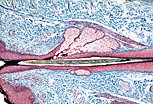

| 此视野显示皮脂腺、立毛肌与毛囊的位置关系。皮脂腺由毛囊上皮壁向外突出发育而成。立毛肌由平滑肌细胞构成,一端附着于皮脂腺下方的毛囊鞘,另一端插入乳头层真皮;其收缩可使毛囊内的毛发竖立。 | |

| 皮脂腺的分泌单位呈泡状,基底附着于基膜。基膜覆盖皮脂腺基底部的区域负责补充因全浆分泌而脱落的细胞,因此仅该区域可称为生发层。分泌单位形似装满细胞的囊,通过短的开口将分泌物排入毛囊(本切片中毛囊腔不可见)。 | |